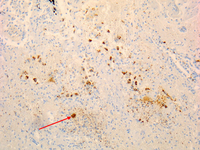

Coxiella burnetii chronic lymphadenitis: immunohistochemistry. Note the isolated infected cell (monocytes/macrophages) in the lymph node. Brown coloration identifies bacteria in monocytes/macrophages

Hubert Lepidi, Institut Hospitalo-Universitaire Méditerranée Infection